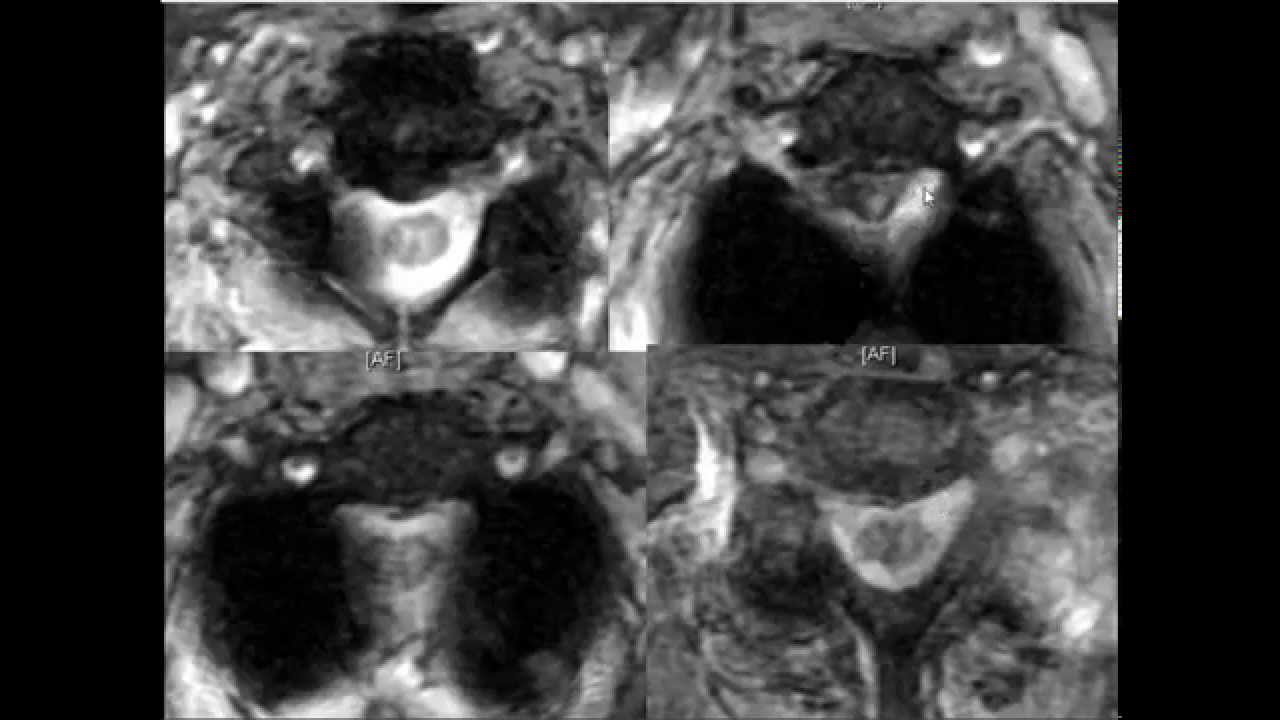

Spine Lecture: Ossification of the Posterior Longitudinal Ligament OPLL